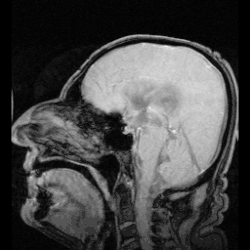

Le liquide cérébrospinal (LCS), ou liquide céphalo-rachidien (ou céphalorachidien) (LCR) en ancienne nomenclature, est un liquide biologique transparent dans lequel baignent le cerveau et la moelle spinale. Il est contenu dans les méninges, plus précisément entre la pie-mère (qui recouvre le système nerveux central) et l'arachnoïde (qui tapisse le versant interne de la dure-mère), c'est-à-dire dans l'espace sous-arachnoïdien. C'est également le liquide qui circule dans les quatre ventricules cérébraux, à l'intérieur du cerveau, dans le canal central de la moelle spinale puis au-delà du tube neural jusqu'au cul-de-sac dural.

Le LCS circule librement dans le système ventriculaire et les méninges, à travers un circuit continu et ne présente pas de poche isolée de liquide en stagnation, passant par les trous de Monro pour aller dans le 3e ventricule, traversant ensuite l'aqueduc de Sylvius pour arriver dans le 4e ventricule. De là, deux possibilités s'offrent à lui : soit il descend autour de la moelle spinale, soit il sort par l'ouverture médiane de Magendie et les trous de Luschka au niveau du toit du 4e ventricule pour passer dans l'espace sous-arachnoïdien.

Si quelque chose (saignement, infection, tumeur, etc.) fait obstacle à son drainage, le LCS s'accumule dans les ventricules[1]. Une pression supérieure à 20 cm d'eau témoigne d'une hypertension intracrânienne (HTIC)[3]. On appelle hydrocéphalie une dilatation des espaces ventriculaires ou sub-arachnoïdiens par hypertension du LCS qui les occupe normalement. Chez le nouveau-né (os du crâne non soudés liés par des fontanelles), l'hydrocéphalie provoque une augmentation du volume de la tête par extension, alors que chez l'adulte (os du crâne soudés en boite inextensible), le LCS provoque des lésions cérébrales[1] par compression.